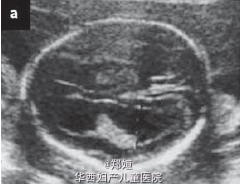

26岁女性,G2P1,单绒毛膜双胎妊娠,孕18+6周,超声提示只有一个胎儿有心跳

超声提示存活的那个胎儿有双侧的脑室扩大(11mm) 羊膜穿刺术提示核型正常 告知患者脑室增大提示宫内的胎儿死亡合并另一个神经系统损害 患者要求继续妊娠